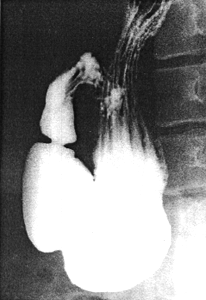

Case 20.2. R.G., 10 day old male infant was admitted for persistent vomiting. Upper gastrointestinal barium study showed a constant, string-like narrowing 2.0 cm in length in the pyloric region, clearly limited to the sphincteric cylinder (Fig. 20.2). It was associated with a concave indentation of the base of the duodenal bulb, the appearance resembling infantile hypertrophic pyloric stenosis. At laparotomy no pyloric tumor was found. There was some kinking of the duodenum, which was corrected, and in view of the radiologic findings a pyloromyotomy was done. A naso-jejunal tube was inserted and recovery was uneventful. The final diagnosis of the pyloric narrowing was spasm of the pyloric sphincteric cylinder.

| Fig. 20.2. Case R.G. Constant spasm of pyloric sphincteric cylinder, simulating infantile hypertrophic pyloric stenosis. At operation no muscular hypertrophy was found |